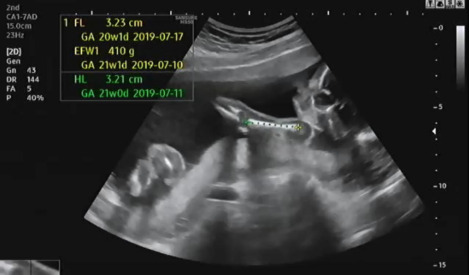

그다음 허벅지와 팔 길이를 측정하는데 다행히 전체적으로 주수에 알맞게 성장 중이라고 의사가 설명했다.

허벅지 길이를 측정하고 아래를 보면 발가락의 개수를 확인했다. 양측 모두 다 발가락 5개 있는지 확인했다. 초음파를 보는데 햇님이가 불편한지 여기저기 발로 밀어대는 모습을 볼 수 있었다.